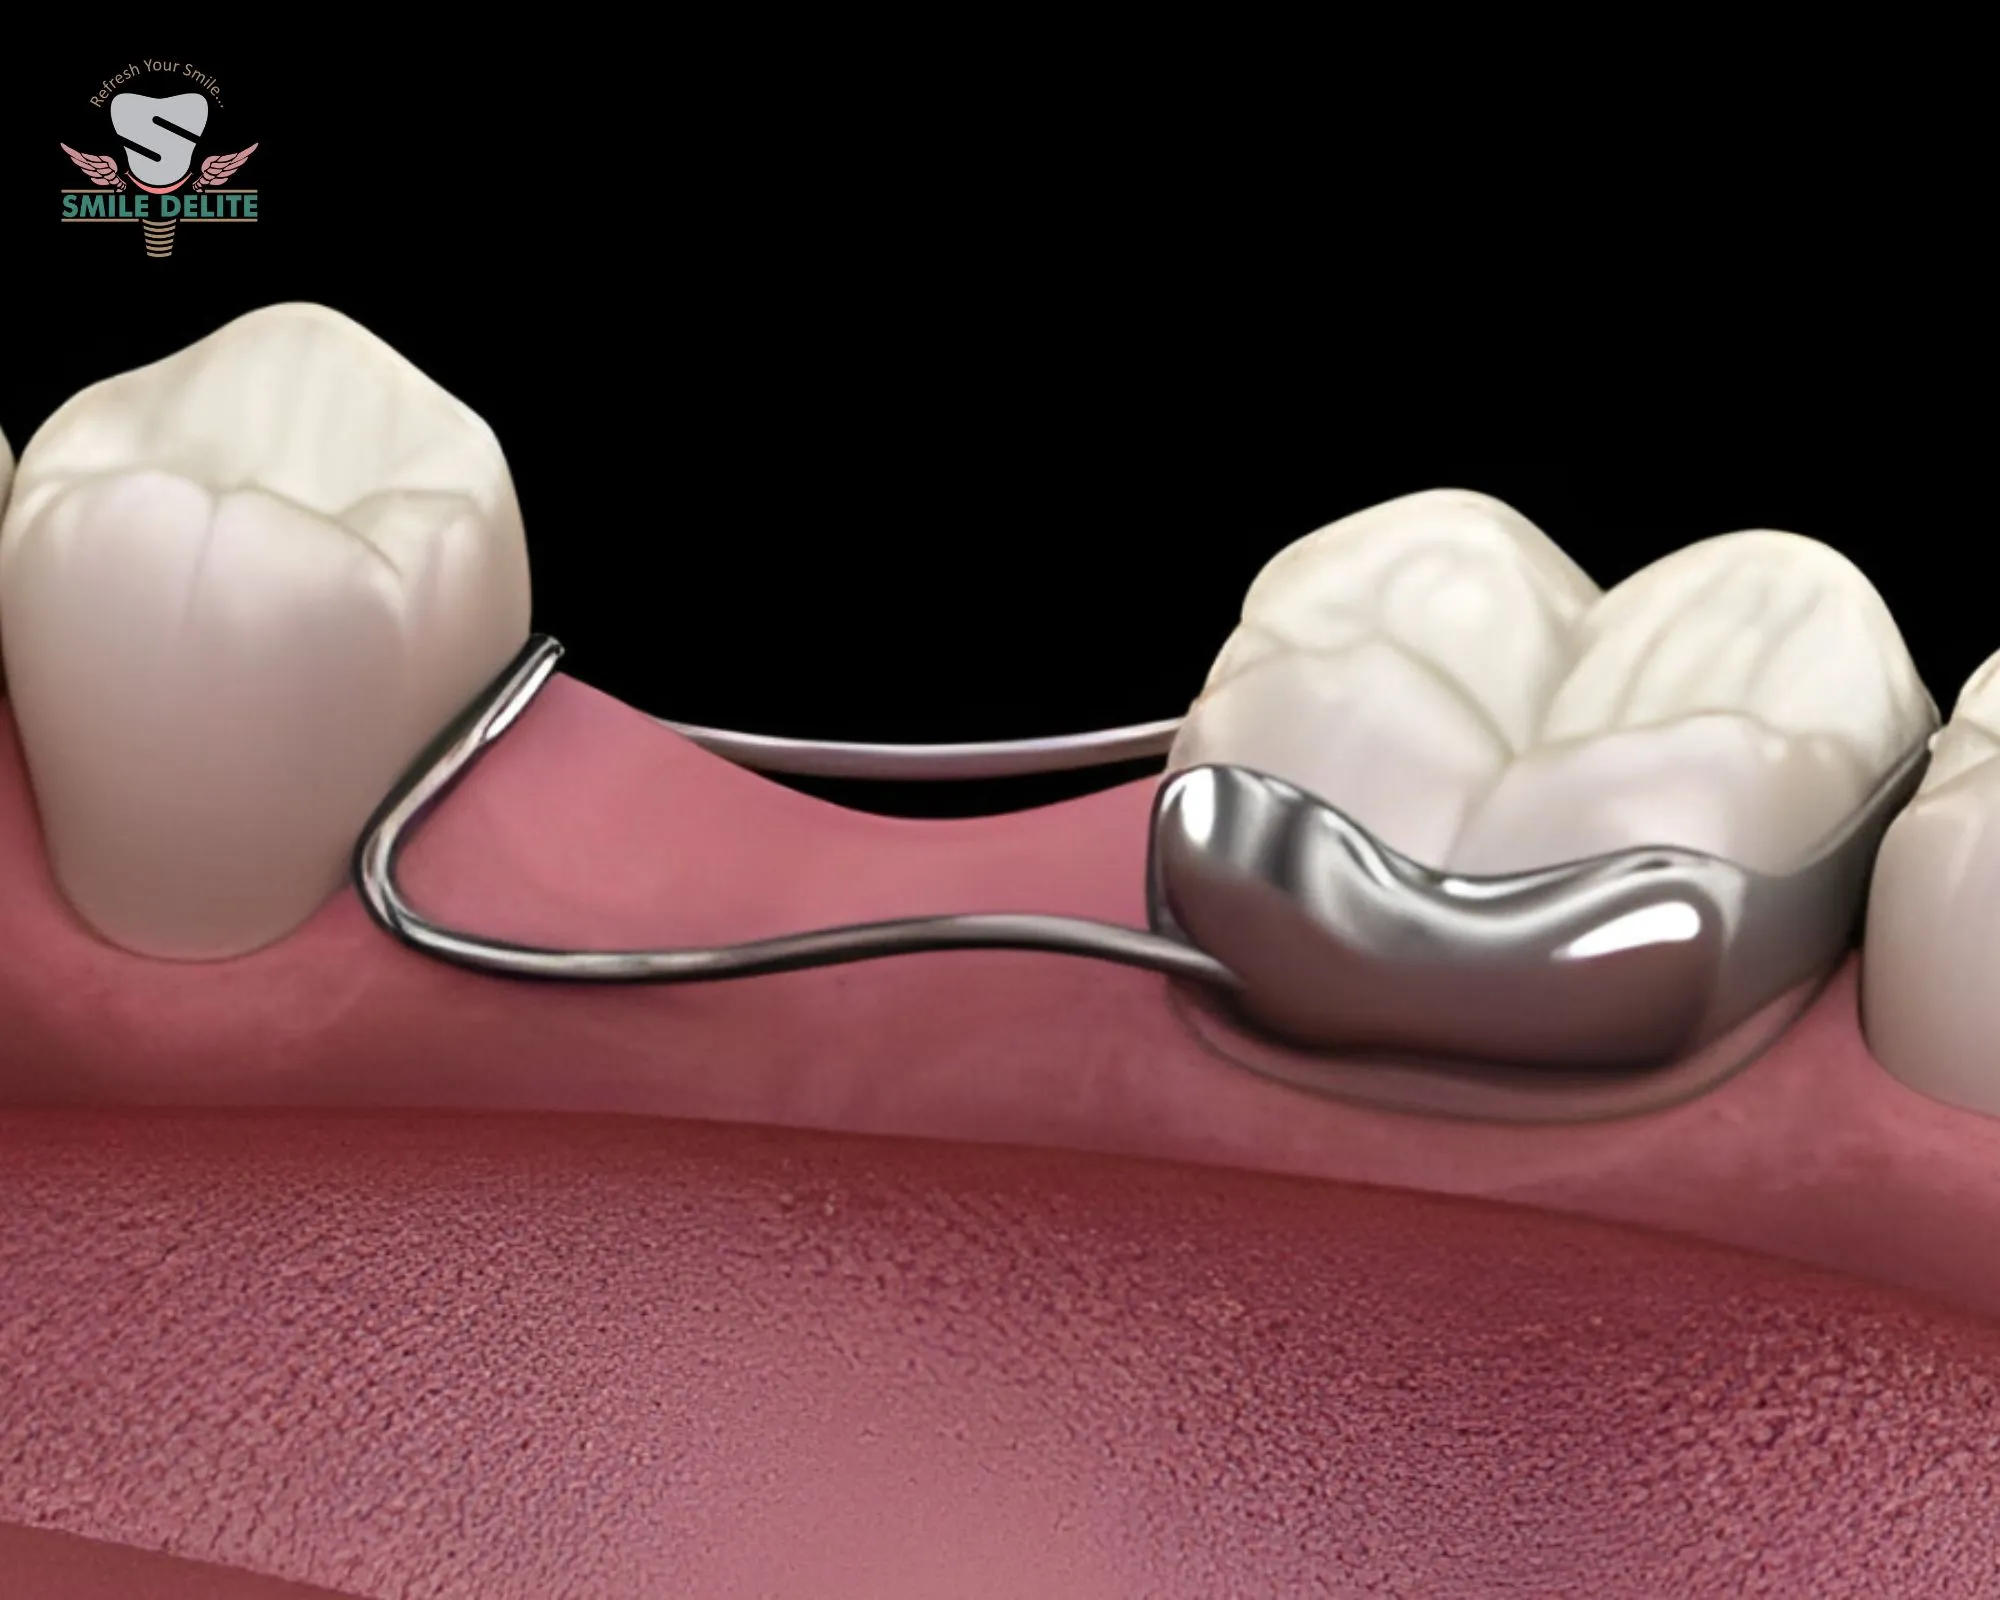

Yes. We provide child-friendly dental care including preventive treatments, space maintainers, and habit correction.